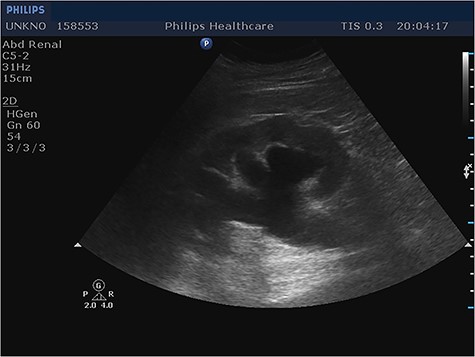

Given the fact that the patient was still hemodynamically stable, and in order to identify preoperatively the content of the incarcerated hernia sac, prompt imaging with ultrasound was considered necessary. Imaging revealed the protrusion of the entire bladder through the right internal inguinal ring and extending into the scrotum (Fig. 1), as well as hydronephrosis of the right kidney (Fig. 2), justifying the patient’s renal dysfunction.

Longitudinal ultrasound image of the inguinal canal revealed a hernia that contained the entire urinary bladder. Notice the urothelium (arrow), as well as a great amount of debris (star).